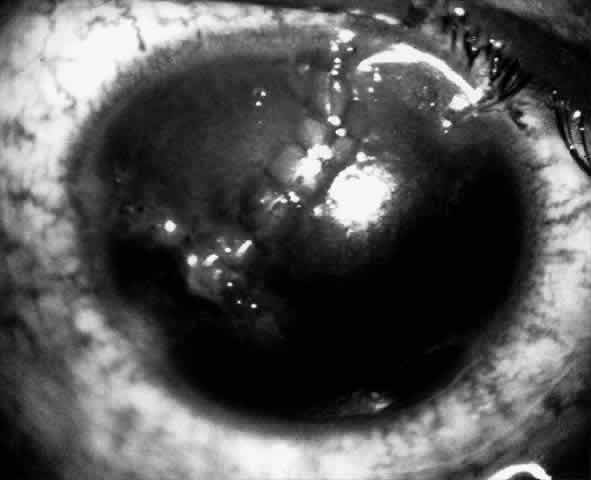

Children who have traumatic cataracts with corneal lacerations are well served by this procedure because the injury often destroys the capsular support that can be used to stabilize an intraocular lens.16–18 The epikeratophakia graft provides structural support for the weakened cornea and minimizes the induced irregular and regular astigmatism, in addition to correcting the optical error (Figs. 3 AND 4).

Fig. 4. Same patient as in Figure 11, with epikeratophakia lenticule in place 3 months after surgery. (Morgan KS, Ellis GS, Marvelli TL, Arffa RC: Epikeratophakia in children. with traumatic cataracts. J Pediatr Ophthalmol Strabismus 23:108–113, 1986)